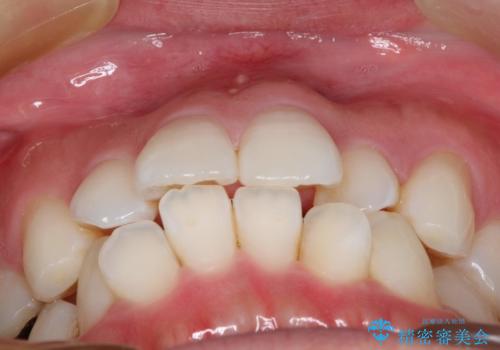

フルリンガル矯正 非抜歯でガタつきを整える

- フルリンガルワイヤーによる非抜歯治療を計画しました。

フルリンガルは違和感も強く操作も煩雑になるため、あまりおすすめはしていませんが、お仕事の都合などでどうしても装置を付けられない&マウスピースを管理することができない、場合はやむなく選択することもあります。